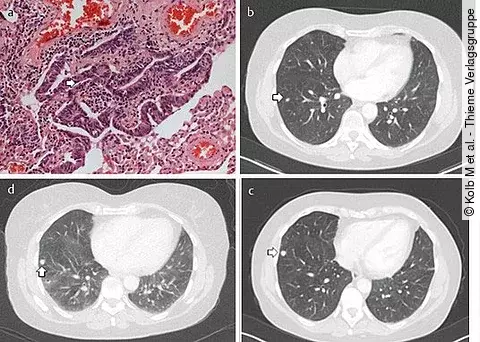

Bislang werden Lungenkrebspatienten, die Hirnmetastasen aufweisen, standardmäßig mit einer Ganzhirnbestrahlung behandelt. Doch das könnte sich bald ändern. In dieser Studie hatten EGFR-mutierte NSCLC-Patienten ein signifikant besseres PFS, wenn sie statt der Bestrahlung eine EGFR-Inhibition mit Icotinib erhielten.